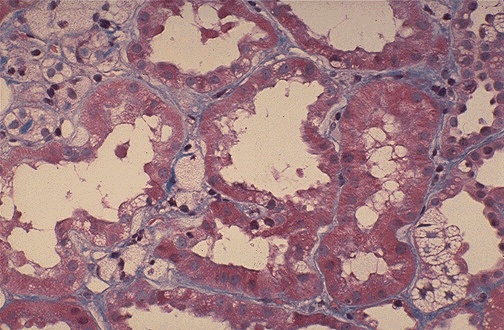

| This is a type of hereditary nephritis known as Alport syndrome in which patients may also manifest nerve deafness and eye problems. The renal tubular cells appear foamy because of the accumulation of neutral fats and mucopolysaccharides. The glomeruli show irregular thickening and splitting of basement membranes. |